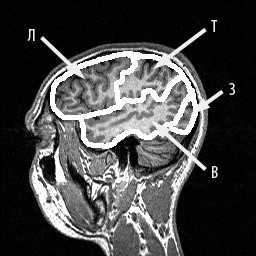

МРТ головного мозга. Границы лобной, теменной, височной и затылочной долей на сагиттальном срезе.

МРТ головного мозга. Границы теменной доли на медиальном сагиттальном срезе.

МРТ головного мозга. Границы затылочной доли на медиальном сагиттальном срезе.